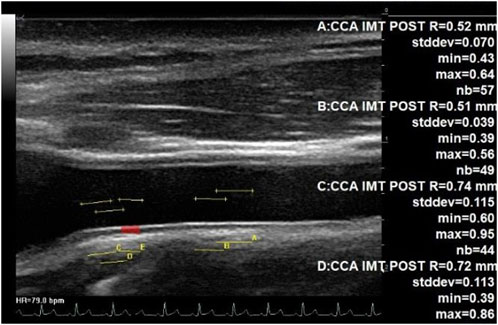

For all assessments, the ultrasound probe was located on the right anterior surface of the neck, in a neck long-axis orientation, perpendicular to the skin and in contact with the collar bone, and then moved forward by some cm to the bifurcation. In both cases, the probe transducer was oriented by the expert on the ground until the CC artery posterior intima appeared clearly within the image. The IMT was then measured on this view at the carotid bulb area (beginning of the bifurcation) and in the middle of the image using an automated detection of the intima and vessel wall limits (Figure 1).

Figure 1. IMT measurement at the middle part of CC and at the bulb area. Echographic image of the common carotid artery up to the bulb area (beginning of bifurcation) at the left, showing automated assessment of the IMT. Each of the four measurements was completed on a total of 44 to 57 adjacent locations along the carotid posterior wall. The IMT changed from 0.51 mm (middle part of CC) up to 0.74 mm (beginning of the bifurcation).

The CC artery IMT close to the carotid bulb was increased inflight and 4 days after returning to Earth in the study. This is consistent with previous studies that have also shown increased carotid IMT with long-duration spaceflight (Arbeille and Provost, 2016; Arbeille et al., 2017b). However, in contrast to these findings, when the IMT was measured further away from the bulb (Figure 1), only a trend toward a greater value with spaceflight was found. A recent spaceflight study (Lee et al., 2020) found no significant change in carotid IMT with spaceflight; moreover, the amplitude of the IMT increase was found to be lower than that in our first 6-month inflight study (Arbeille and Provost, 2016). However, this could reflect a difference in the measurement location (Figure 1) from the point of the carotid bifurcation and the difference between the populations investigated. The location of the measuring point may impact the IMT value due to a gradual transition from a large elastic artery (middle CC) to a predominately muscular artery (bifurcation and internal carotid (Figure 1) (Kamenskiy et al., 2015) and indicate site-specific differences in adaptations and remodeling with spaceflight.